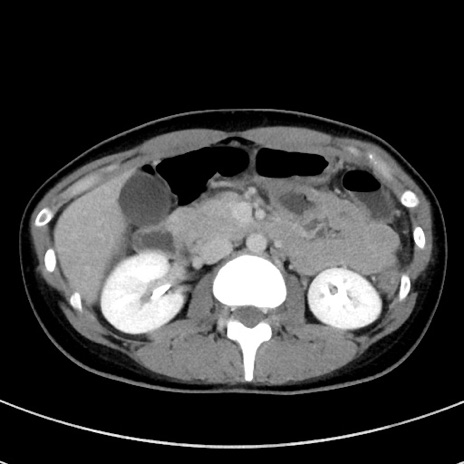

症例17(横断像)

冠状断像

【症例】20歳代女性

【主訴】嘔吐、下腹部痛

【現病歴】昨日夕食後に嘔吐し下腹部痛が出現。本日になっても嘔吐持続し改善しないため来院。

【身体所見】意識清明、BT 37.2℃、BP 108/67mmHg、腹部:平坦、やや硬、下腹部正中から右にかけて圧痛あり、反跳痛軽度あり、tapping pain(+)。

【データ】WBC 13600、CRP 14.94